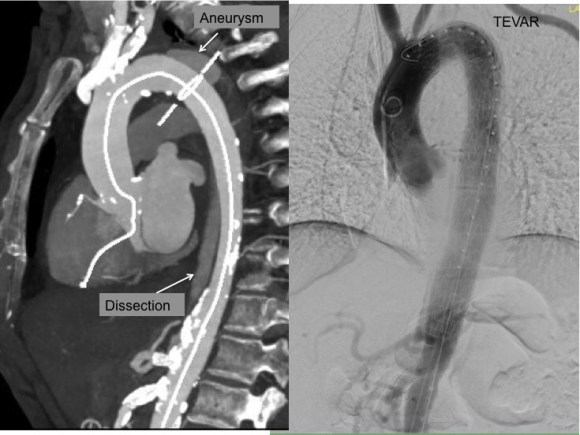

This has several advantages over conduit creation which can be a morbid and high risk procedure in patients who require minimally invasive approach. A graft is avoided. The artery is over 8mm in diameter where with stenting up to 8mm with an occlusive plaque, the danger of rupture is present, and often ballooning is restricted to 6mm-7mm. This is insufficient for many TEVAR grafts and TAVR valves.

His operation was performed via an anterior approach with the patient supine. A tube graft repair was performed expeditiously and included resecting the dissection flap up to the clamp. Care was taken to avoid injury to the renal stent. The proximal anastomosis went well – the dilated aorta yet had strong tissue strength. A felt strip was used to buttress the aortic side of the anastomosis. The estimated risk of paralysis was less than 1% and risk of death was less than 2%. The patient recovered uneventfully and went home on POD 5.